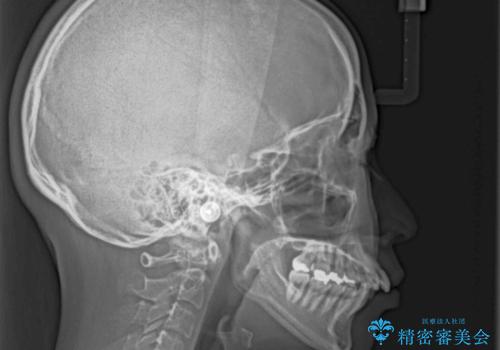

- 八重歯と上の前歯が出っ歯になっていることを気にして来院された患者様です。

横から見た際の口元の飛び出した印象も改善したいとのことで、上下左右の第一小臼歯4本を抜歯し、ワイヤー装置にて抜歯矯正を行うこととしました。

前歯の変色している歯は、神経組織が壊死していたため、矯正治療前に根管治療を実施し、矯正治療後にオールセラミッククラウンにて補綴治療を行うこととしました。

順調に歯が動き、補綴治療も含め2年弱で治療を終えることができました。